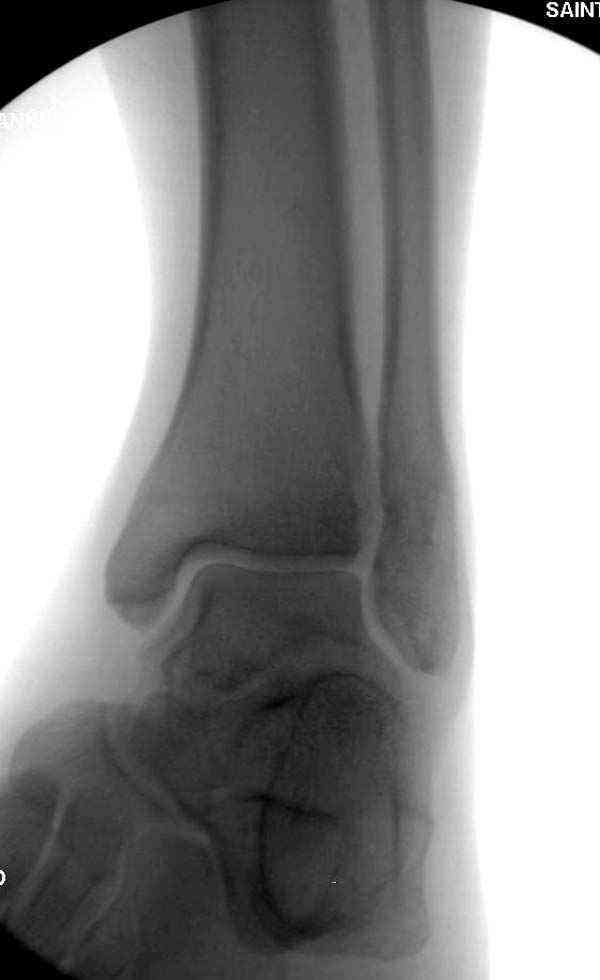

Случай прошлого года:пациентка-молодая ,крупная женщина ,30лет.Травма в начале апреля 2009г-пронационный перелом лодыжек с подвывихом стопы.Ко мне обратилась через 35 дней,прооперирована 22.05.2009г.Внутренняя лодыжка фиксирована по Веберу,наружная реконструктивной пластиной с наложением болта-стяжки.Иммобилизация "сапожок" в течении месяца,затем пригипсовано "стремя".Гипс снят 10.07.2009г

Достаточно быстрое восстановление функции.В октябре 2009г-почувствовала боль,в области рубца над гайкой открылся свищ.На Р-граммах-консолидация переломов и смещение гайки по стяжке.10.11.2009г-конструкции удалены,санация,заживление ран.В настоящее время пациентку ничего не беспокоит.На операции-раскручивание гайки-болталась на конце стяжки.Вопросы:какой механизм раскручивания и что я неправильно сделал?Свои версии:1)в области синдесмоза успела образоваться рубцовая ткань,которая при движении в суставе"пружинила",поскольку голеностопный сустав является спиральным, то и биомеханика подобна кривошипному механизму.2)Реконструктивная пластина не "реконструировалась" по форме лодыжки.Наложил,как есть.То есть подпружинивала сама пластина.Ну,это мои догадки.Что нужно,чтобы избегать впредь таких,пусть и не "страшных"осложнений:Рассверливать через лодыжку область синдесмоза?Ставить шайбу-гровер?Тщательно моделировать пластину?Прилагаю сравнительные снимки-сразу после операции и перед удалением конструкции.

Визуально никаких вопросов по репозиции не было.Да и на основании чего сомнения,что наружная лодыжка не полностью репонирована или прорезалась проволка ???Я не вижу...Снимок после репозиции справа.

Раз ,есть желание посмотреть другую проекцию выкладываю-ну лучшего качества нет...